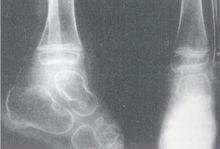

早期(病程1年左右)X線僅顯示軟組織腫脹,關節周圍骨質疏鬆,關節附近呈現骨膜炎。晚期才能見到關節面骨破壞,以手腕關節多見。